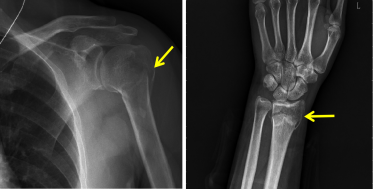

45岁的王女士1月前不慎跌倒,左侧肩部及腕部疼痛、肿胀、关节活动受限,就诊后行X线检查提示左侧肱骨近端、桡骨远端骨折(见图1),遂行手术治疗,术后切口愈合良好,顺利拆线出院后,于家中自行功能训练。但王女士逐渐发现,术区胀痛并未缓解,且术区皮肤摸着发硬、发烫,连日常生活中简单的洗脸、梳头、握拳动作都不能完成,王女士很是苦恼,复查片子显示骨折愈合良好(见图2),遂抱着试一试的心态就诊我科门诊。

图1. 左侧肱骨近端、桡骨远端骨折